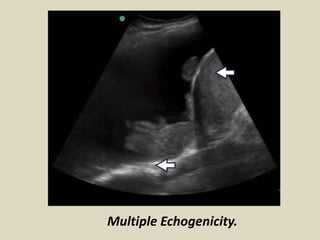

Multiple Echogenicity.

Terminology. Echogenicity. Hypo-Hyper-Iso-An Echoic The circleis Hyperechoic to the surrounding tissue. The circle is Hypoechoic to the surrounding tissue.

• 47.

The circle isIsoechoic to the surrounding tissue. The circle is An Echoic to the surrounding tissue.